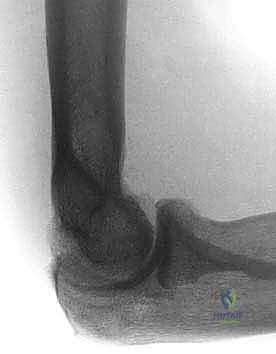

- الأشعة السينية (X-rays): لتقييم شكل العظام، البحث عن الكسور القديمة، وتحديد أماكن النتوءات العظمية والأجسام الحرة الكبيرة.

- الفحص النهائي للمدى الحركي: أثناء وجود المريض تحت التخدير، يقوم الدكتور هطيف بتحريك المرفق للتأكد من استعادة المدى الحركي الكامل والوظيفي بسلاسة ودون مقاومة.